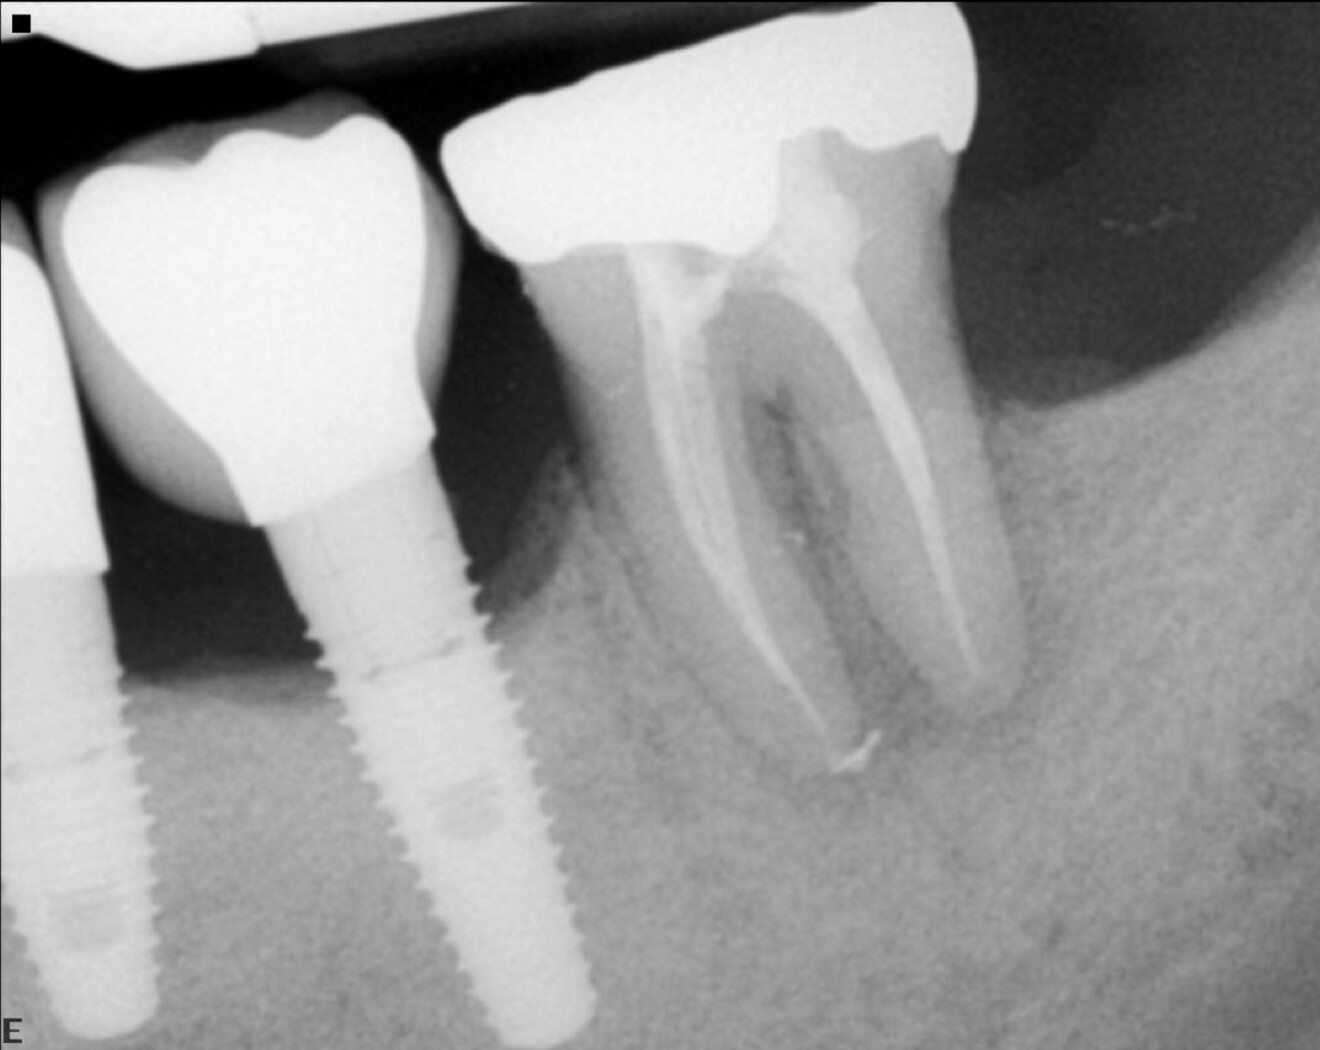

A patient with a periodontal issue was referred for the treatment of a maxillary and a mandibular molar. The maxillary molar was necrotic, and the preoperative radiograph showed a severely calcified pulp chamber and blocked root canal entrances (Fig. 7).

Fig. 7: Pre-op radiograph showing a maxillary first molar with a very calcified pulp chamber and narrow canals.

Fig. 8: Post-op radiograph of the root canal treatment done using Adaptive Motion with the narrow canal file sequence.